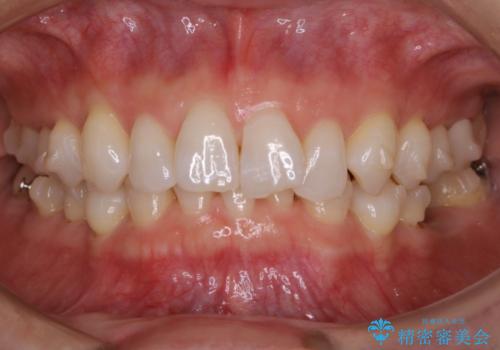

【抜歯】矯正治療とインプラントで正常な噛み合わせを実現

- 30代 女性

- マウスピース(インビザライン)

- 2年2ヶ月

- 元々は矯正治療を主訴にご来院されました。

治療を始めるにあたり、精密検査を受けていただき全体の状況を把握したうえで矯正治療の計画を立てることとなりました。

その過程で左下の6番目の歯は治療が必要な状態であることが分かり、被せ物を外して内部を確認してみると根が破折してしまっていることが判明しました。

歯が深い位置で破折している場合は基本的には抜歯が選択されます。

様々な治療プランを患者さんと相談させて頂き、最終的にインプラントで噛み合わせを回復させていくこととなり、まず悪くなっている歯を抜歯することから開始しました。